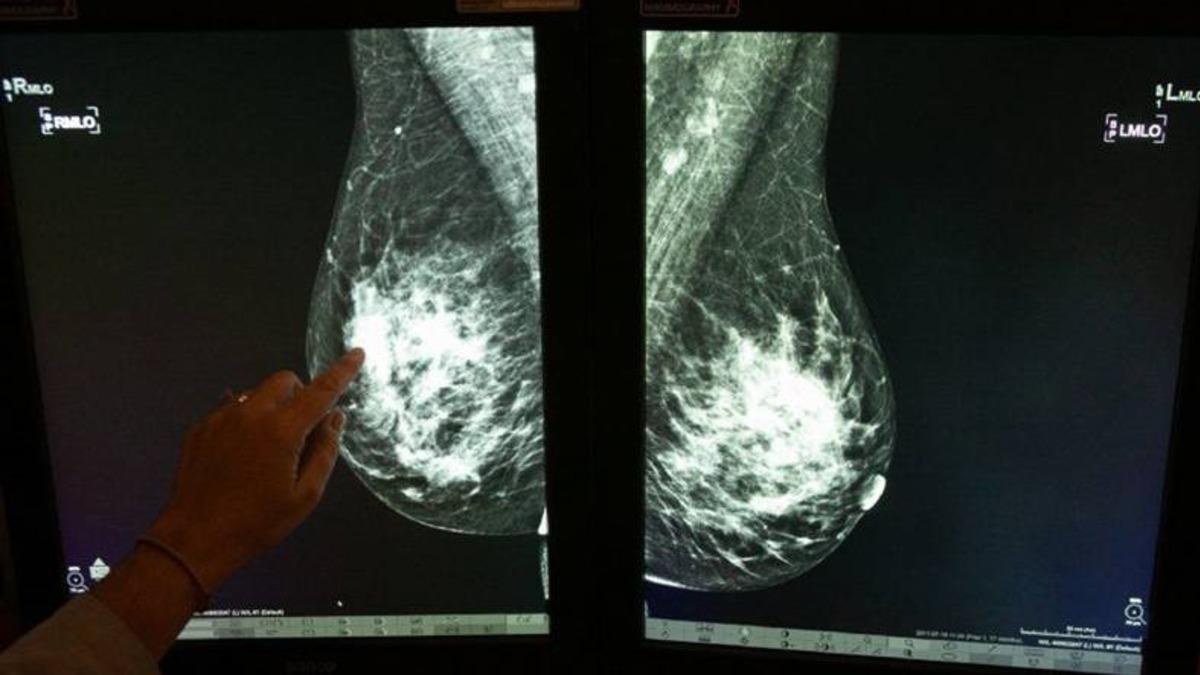

Google araştırmacıları şu günlerde meme kanserini daha hızlı tespit edebilmek amacıyla kullanılacak bir algoritma üzerinde çalışıyor. Araştırmanın sonuçlarıyla ilgili konuşmak için erken olsa da, yapılan yorumlar hatalı teşhislerin azaltılmasına ve doktor eksikliğinin giderilmesinde yardımcı olacağı yönünde.

Google’ın sahip olduğu DeepMind’ın, son yıllarda tıp alanında kullanılacak yapay zekalar geliştirmek için çeşitli sağlık kuruluşlarıyla çalıştığı biliniyor. Yeni sistemi geliştirmek için ilk olarak 76.000 İngiliz kadından alınan verileri ve ABD’den 15.000 tarama örneğini kullanılarak eğitildi. Yapay zekadan elde edilen sonuçlar gerçek sonuçlar ve radyolog yorumlarıyla karşılaştırıldığında oldukça tutarlı sonuçlarla karşılaşıldı.

Araştırmaya göre yapay zeka, meme kanserini tek bir uzman radyologla aynı doğrulukta tespit edebilecek. Ayrıca edinilen sonuçlara göre, uzmanlara kıyasla yanlış negatif sonuçlarda ABD’de yüzde 5,7 Birleşik Krallık’ta ise 1,2 oranında azalma görüldü. Böylece erken teşhisin de önü açılmış olacağı gayet açık.